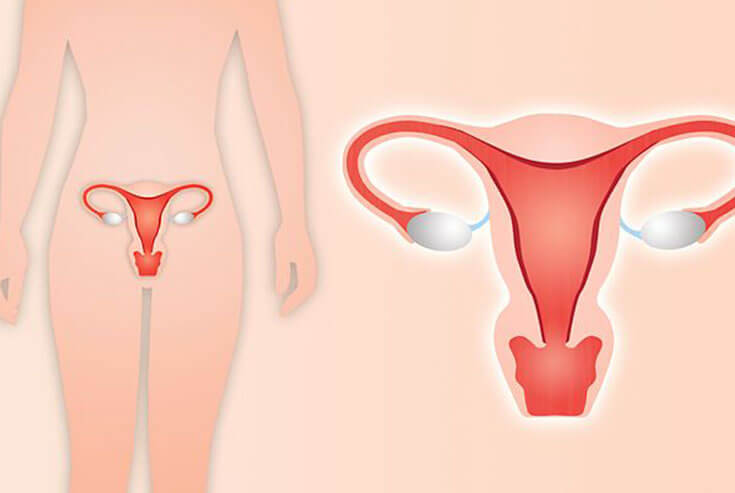

Gynecological conditions can significantly affect a woman’s health, comfort, fertility, and overall quality of life. When medications and conservative treatments are not enough, surgical intervention may be required. Modern gynecology surgery is safer, less invasive, and more effective than ever before.

When is Gynecology Surgery Required?

Gynecological surgery may be recommended for:

- Uterine fibroids

- Abnormal uterine bleeding

- Ovarian cysts

- Endometriosis

- Ectopic pregnancy

- Pelvic pain

- Infertility

- Uterine prolapse

- Cancer-related conditions

- Unwanted pregnancy (as per legal guidelines)

Gynecological Sonography Services

Bhagyoday Women’s Care Hospital is a trusted Gynec Sonography Clinic in Ahmedabad offering ultrasound for:

- Pelvic pain diagnosis

- Irregular periods

- PCOS / PCOD evaluation

- Fibroids and ovarian cysts

- Abnormal bleeding

- Infertility evaluation

- Uterine abnormalities

- Post-menopause issues

Types of Gynec Ultrasound

- Transabdominal Pelvic Ultrasound

- Transvaginal Ultrasound

- Follicular Monitoring

- Pelvic Ultrasound for Uterus & Ovaries

These scans help doctors make accurate diagnoses and plan the right treatment.